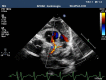

Case report: This case report describes 3-month-old boy admitted to the hospital because of feeding problems. The boy was born at term, with birth weight 3200 g, and was 10 points in Apgar score. He was breast-fed from birth. From the seventh week of age, his mother observed his increasing difficulties with feeding. Physical examination revealed pale skin, diminished heart sounds, tachycardia, cardiomegaly, and hepatomegaly. Results of urine and blood tests and ultrasonography of the central nervous system and abdomen were normal. The chest radiography showed cardiomegaly and electrocardiogram revealed anterolateral myocardial infarction. On echocardiography, an anomalous left coronary artery arising from the pulmonary artery was found. The life-saving treatment of choice was immediate surgical reimplantation of the left coronary artery to the aorta.